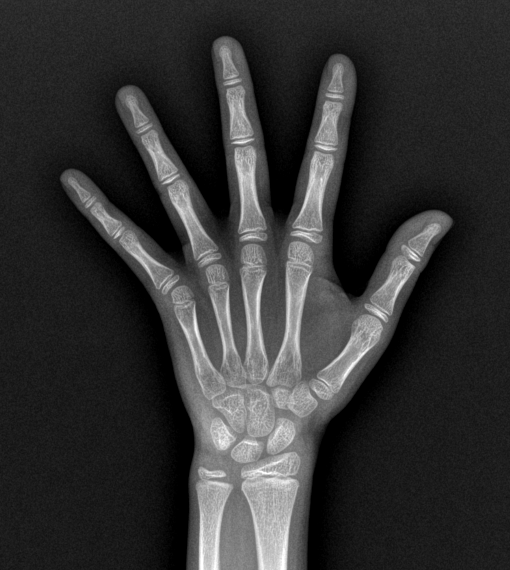

骨龄是评估骨骼成熟程度的客观指标,我们通常通过左手腕部X光片判定。相比实际年龄,骨龄更能反映儿童的生理成熟度与生长潜力。

图源:我女儿的骨龄片